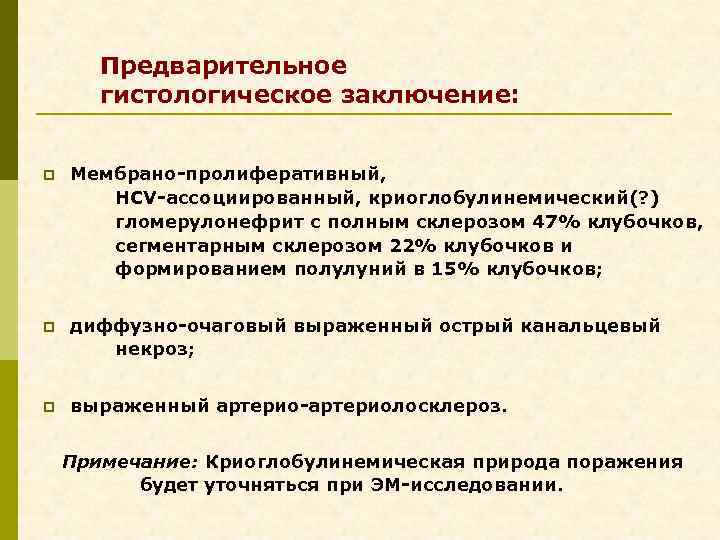

Иммунофлюоресцентное исследование: p Клубочки: Ig. G (2+), Ig. M (3+), C 3 (2+), kappa (3+), lambda (1 -2+) - диффузная, субэндотелиальная и интракапиллярная, крупно-гранулярная экспрессия; p Стенки артериол: C 3 (2+); p Цилиндры: Ig. G (2+), Ig. A (3+), Ig. M (2+), C 3 (3+), kappa (3+), lambda (2+); p Реабсорбированные белковые капли: kappa (3+).

Предварительное гистологическое заключение: p Мембрано-пролиферативный, HCV-ассоциированный, криоглобулинемический(? ) гломерулонефрит с полным склерозом 47% клубочков, сегментарным склерозом 22% клубочков и формированием полулуний в 15% клубочков; p диффузно-очаговый выраженный острый канальцевый некроз; p выраженный артерио-артериолосклероз. Примечание: Криоглобулинемическая природа поражения будет уточняться при ЭМ-исследовании.

Заключение p Мембрано-пролиферативный гломерулонефрит, криоглобулинемический, ВИЧ-ассоциированный, на фоне гепатита С